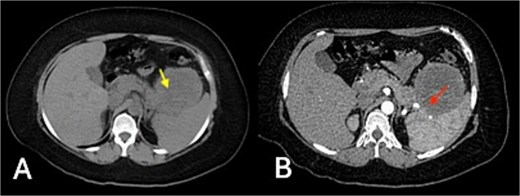

Triple-phase contrast-enhanced computed tomography (CT) of the upper abdomen demonstrated an exophytic, well-defined, lobulated lesion of the gastric fundus measuring 83 × 72 × 79 mm (Fig. 1).

Triple-phase contrast-enhanced CT of the upper abdomen: (A) non-contrast phase showing an exophytic, well-defined, lobulated lesion of the gastric fundus (83 × 72 × 79 mm) with isodense attenuation (20 HU) (yellow arrow); (B) arterial phase revealing mild heterogeneous enhancement (up to 35 HU) and central hypodensity, with loss of interface between the mass, pancreatic tail, and spleen (red arrow indicates area of interface loss).